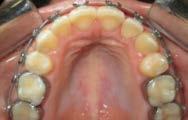

Figura 11. Fotografías intraorales finales.

Figura 12. Antes vs. después.

Figura 12. Antes vs. después. (Continuación)